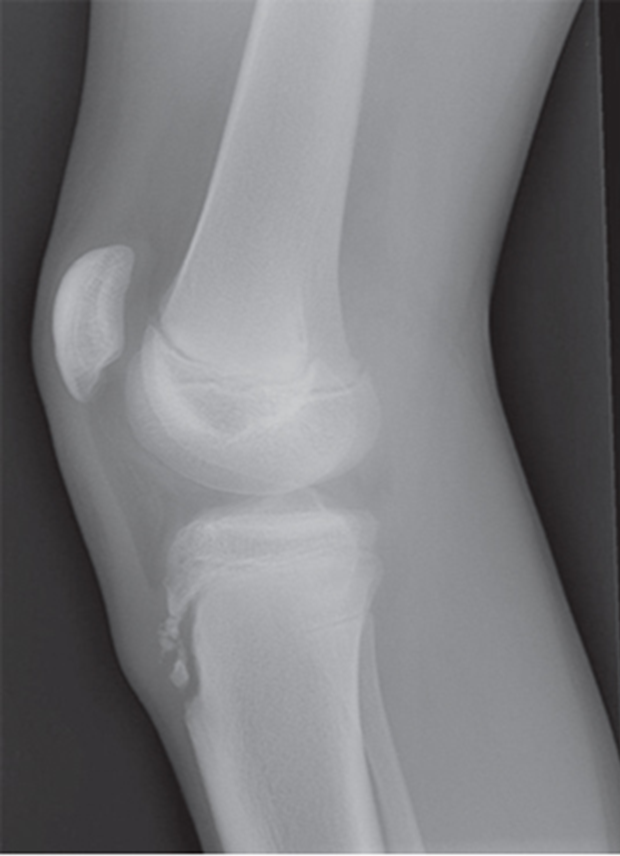

Trauma and Non-Trauma Lateral Knee (Mediolateral)

•Evidence of proper collimation and the presence of a side marker placed clear of the anatomy of interest

•Knee flexed 20 to 30 degrees in true lateral position as demonstrated by femoral condyles superimposed (locate the more magnified medial condyle)

•Anterior surface of medial condyle closer to patella results from over-rotation toward the image receptor (IR).

•Anterior surface of medial condyle farther from patella results from under- rotation away from the image receptor (IR).

•Inferior surface of medial condyle caudal to lateral condyle results from insufficient cephalad central ray (CR) angle.

•Inferior surface of lateral condyle caudal to medial condyle results from too far cephalad CR angle.

•Fibular head and tibia slightly superimposed (over rotation causes less superimposition, and under rotation causes more superimposition)

•Patella in a lateral profile

•Open patellofemoral joint space

•Open joint space between femoral condyles and tibia

•Bony trabecular detail and surrounding soft tissues

over-rotated fibular head is not touching

Patellofemoral joint space is not open (Condyle is in it)

The medial condyle is closer to the patella it is over rotated

Lateral condyle is lower, too much tube angle

Rotation, fibula is under! Which means it is under-rotated. The condyle is in the patella femoral space, the abductor tubercle (medial condyle) , medial condyle is posterior. Central Ray is too superior. NOT ENOUGH